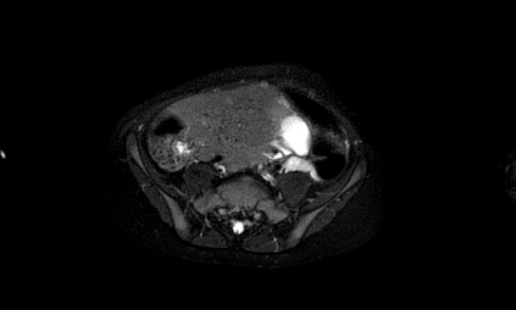

Hình ảnh T1W tăng cường tương phản có ức chế mỡ.

Các vùng tín hiệu cao bị ức chế, điều này cho thấy đó là mỡ.

Lưu ý

mối liên quan chặt chẽ với động mạch mạc treo tràng trên, có thể bị tổn thương

trong quá trình phẫu thuật.

At operation a benign mature cystic teratoma was resected.